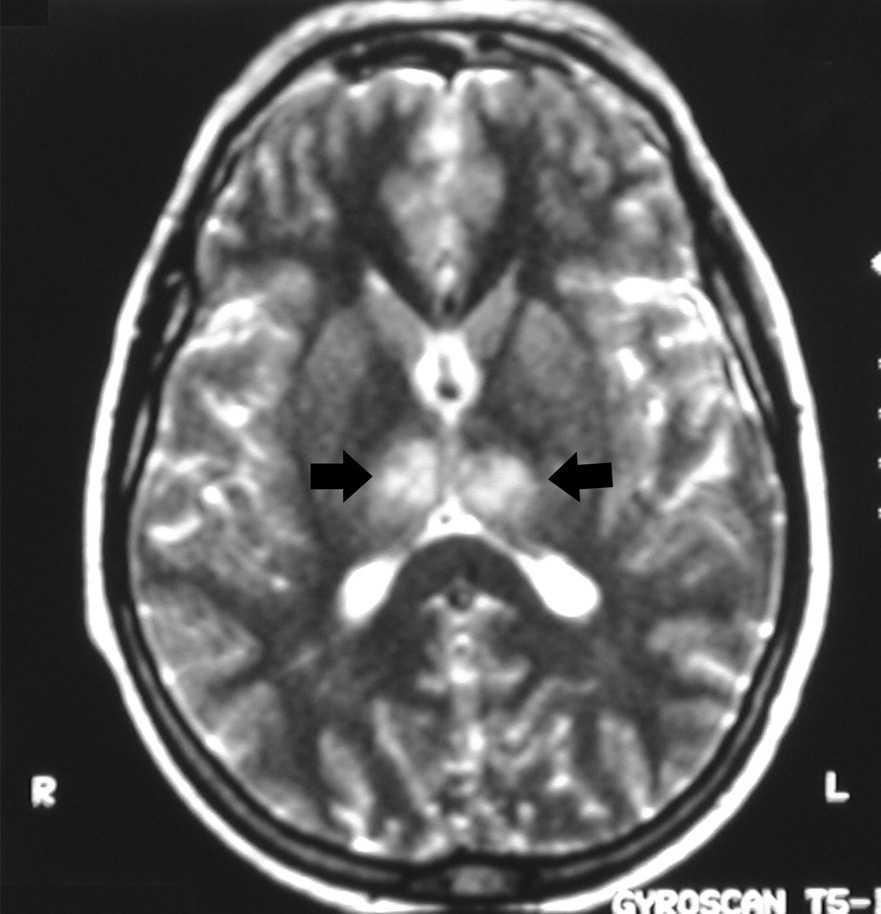

Figura 2. Imagen potenciada en T1, hiperdensidad en ambas regiones talámicas